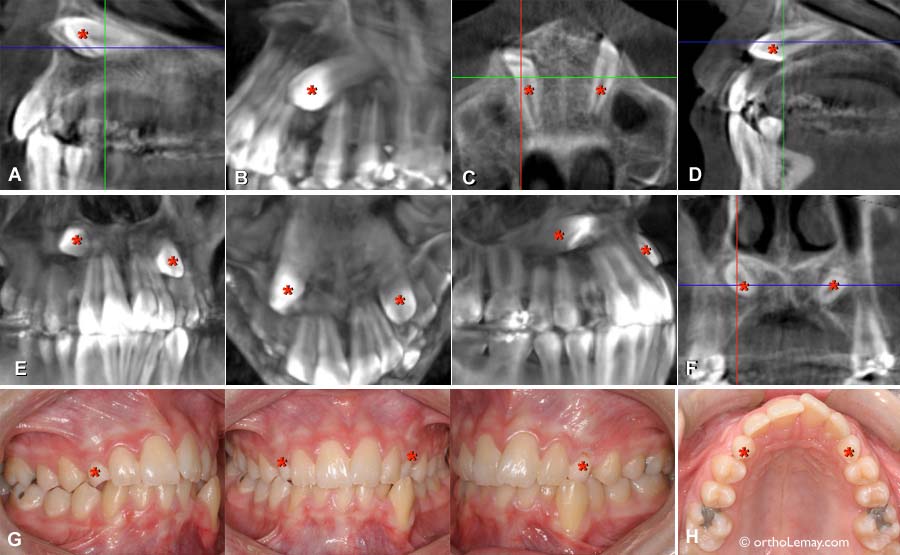

Vue sagittale montrant les canines sous la base du nez

(A, B et D) Vue sagittale montrant les canines sous la base du nez. Les canines incluses sont indiquées avec un astérisque (*) rouge. En (G), les canines temporaires sont indiquées par des astérisques.

(C) Vue axiale qui montre les canines placées à l’horizontale sous le nez.

(E) Autres vues à angles différents.

(F) Coupe coronale où l’on voit très bien les canines juste sous le nez.

(G) Bien que cette malocclusion ne semble pas très sévère, sa gravité est augmentée grandement par la présence des canines incluses.